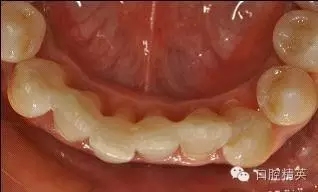

治療后:炎癥得到控制,牙周袋已消除,松動(dòng)度有所改善。

牙周固定后: